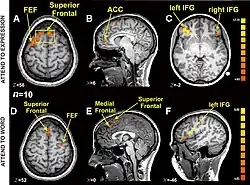

Research using functional magnetic resonance imaging of the brain suggests that cognitive and affective-expressive forms of communication and self-reflection have distinct neural bases.[50] Clinical findings have long suggested that verbalizations are often very incoherent when the individual is trying to put into words something deeply emotional.[51] Identification of words naming emotions (happy, neutral, sad) was found to be faster than identification of corresponding facial expressions. Recognition of face expressions was more difficult to suppress in favor of the recognition of words than vice versa, the two conditions presenting different patterns of brain activation. These experimental results suggest that reading and recognition of face expressions are stimulus-dependent and perhaps hierarchical behaviors, hence recruiting distinct regions of the medial prefrontal cortex.[48]

Research indicates that the representations of faces and objects in ventral temporal cortex are widely distributed and overlapping, face stimuli eliciting response patterns distinct from those elicited by object stimuli.[49]

- ^ a b Ovaysikia S, Tahir KA, Chan JL, DeSouza JF (January 2011). "Word wins over face: emotional Stroop effect activates the frontal cortical network". Front. Hum. Neurosci. 4: 234. doi:10.3389/fnhum.2010.00234. PMC 3020489. PMID 21258644.

- ^ a b Haxby, JV; Gobbini MI; Furey ML; Ishai A; Schouten JL; Pietrini P (Sep 2001). "Distributed and overlapping representations of faces and objects in ventral temporal cortex". Science. 293 (5539): 2425–30. Bibcode:2001Sci...293.2425H. CiteSeerX 10.1.1.381.2660. doi:10.1126/science.1063736. PMID 11577229. S2CID 6403660.

- ^ Moran, JM; Macrae CN; Heatherton TF; Wyland CL; Kelley WM (September 2006). "Neuroanatomical Evidence for Distinct Cognitive and Affective Components of Self". Journal of Cognitive Neuroscience. 18 (9): 1586–1594. CiteSeerX 10.1.1.334.3110. doi:10.1162/jocn.2006.18.9.1586. PMID 16989558. S2CID 12575048.